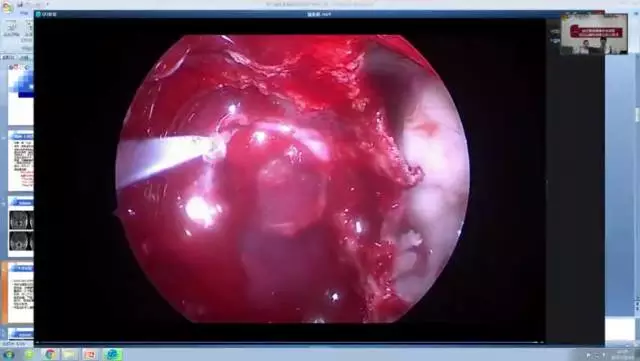

内镜下如遇海绵间窦和海绵窦出血,有什么好的止血建议?